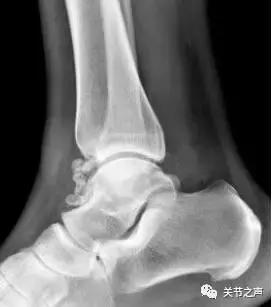

除了肩关节,髋、膝、踝、肘、腕几乎全身各个关节都有可能长珍珠。